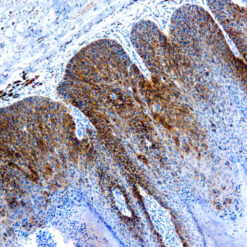

This antibody recognizes insoluble elastin, α-elastin, soluble non-cross linked precursor of elastin (tropoelastin). Elastin is an important polymeric protein of connective tissue that imparts elasticity to vertebrate elastic tissues.

| Clone | BA-4 |

| Immunogen | Bovine α-elastin |

| Positive Control Tissue | Heart, Kidney |